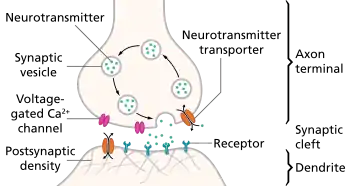

A chemical signal (synaptic transmission) begins with the action potential that propagates down the axon of so-called presynaptic terminal to trigger Ca2+ influx, which causes the synaptic vesicles to fuse and release neurotransmitters, via exocytosis, to the synaptic cleft.[5][6] Released neurotransmitters then bind their specific neuroreceptors at the postsynaptic membrane, or activate their specific ligand-gated ion channels, to fire an action potential that can be either excitatory or inhibitory, depending on the nature of the ligand-gated ion channel. Neurotransmitters are removed from the synaptic cleft by either enzymatic degradation or re-uptake by the same presynaptic neuron, via endocytosis or specific neurotransmitter transporters.[4]

Maintaining a balance between the intracellular and extracellular ionic concentrations at the postsynaptic terminal is critical to normal neuronal function. During oxygen depletion to the brain, two events that initiate, as well as propagate, anoxic depolarization involve excessive cationic influxes, as well as the outflow of ATP, at the postsynaptic terminal.[1] The receptors that allow this influx and outflow are the ionotropic receptors, which are ligand-gated ion channels that bind specific neurotransmitters, released from the synaptic vesicles of the presynaptic terminal, to trigger the opening of the channels, which serve as conduits for cations that, in turn, initiate action potential across the post synaptic terminals of normally functioning neurons.[7]

The key player in the dramatic process of cationic influx is glutamate, an excitatory neurotransmitter that triggers excitotoxicity during anoxic depolarization.[8] A number of ionotropic receptors have been identified as contributing to anoxic depolarization of nerve cell membranes. They include the NMDA receptors, AMPA receptors, P2X7 purinergic receptors, pannexin channels (Panx1), transient receptor potential (TRP) channels, and acid-sensing ion channels (ASICs).[1]

During brain ischemia, glutamate is released in excess from the presynaptic terminal, leading to the uncontrollable opening of the glutamate receptors, including the NMDA and AMPA receptors, which allows for an excessive influx of Ca2+ into the intracellular environment. Purinergic and NMDA receptors activate the pannexin-1 channels, which become hyperactive and allow the release of ATP from the intracellular environment. As the extracellular glutamate and ATP increase, several complexes are activated and converge into apoptotic and necrotic cascade pathways, which cause neuronal damage and death.[1]